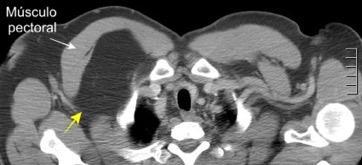

48 MASAS. LIPOMA SUBPECTORAL

Densidad similar al músculo con estriaciones internas de grasa

Hallazgo incidental . Región infraescapular 2% de TC del tórax. Bilateral 60%.

Burt AM et al. Imaging review of lipomatous musculoskeletal lesions. SICOT J2017/ Murphey MD et al. From the archives of the AFIP: benign musculoskeletal lipomatous lesions. Radiographics. 2004